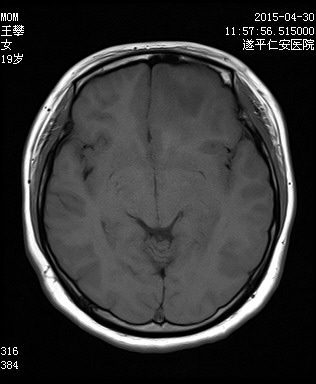

MRI6833:头颅MRI

【结果公布】 女,19岁,头痛恶心一周余,CT显示头颅占位。

左侧额叶占位;多为肿瘤性病变,胶质瘤可能

考虑星形胶质细胞瘤

3-4级胶质瘤可能性大

病理结果 胶质母细胞瘤

考虑 III级-IV级星形细胞瘤可能性大。

星形胶质细胞瘤III级